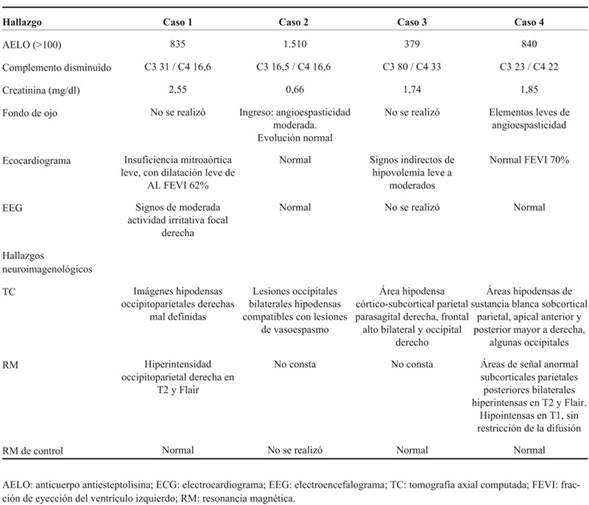

Las características clínicas de los pacientes se muestran en la (Tabla 1). La mediana de edad fue 11,5 años, rango 10 a 13 años. Dos pacientes de sexo masculino y dos de sexo femenino.

Tabla 1: Encefalopatía posterior reversible en el curso de glomerulonefritis aguda posestreptocócica en niños hospitalizados en el Centro Hospitalario Pereira Rossell. Manifestaciones clínicas.